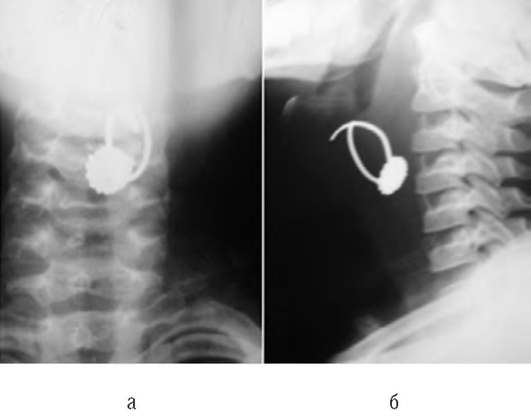

По механизму обструкции дыхательных путей ИТ различают: на необтурирующие просвет, обтурирующие по типу «клапана» и полностью обтурирующие просвет дыхательных путей (рис. 3-7).

ИТ может находиться в носовых ходах, гортани, трахее, бронхах, в ткани самого легкого, в плевральной полости. Несмотря на многообразие клинических симптомов, необходимо выделять наиболее характерные признаки определенной локализации ИТ в дыхательных путях.